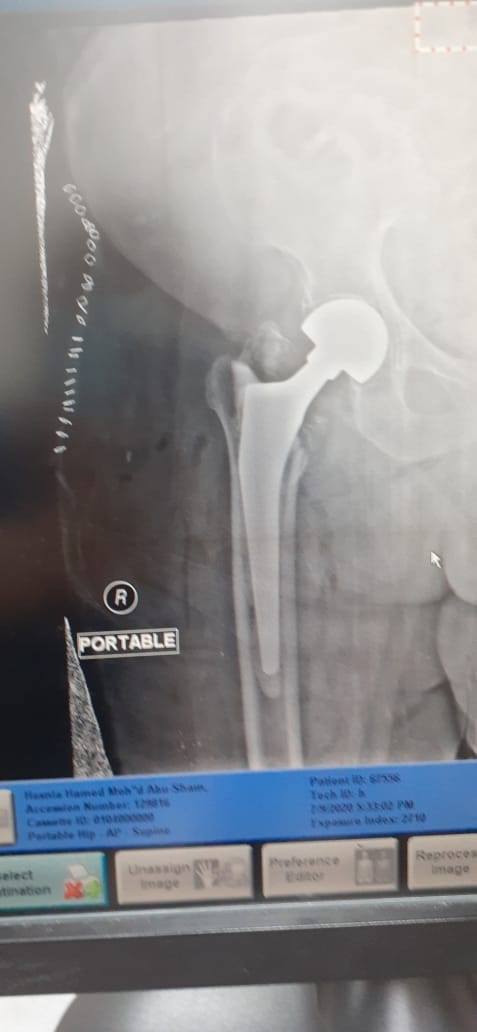

زراعة المفاصل الصناعية ورك و